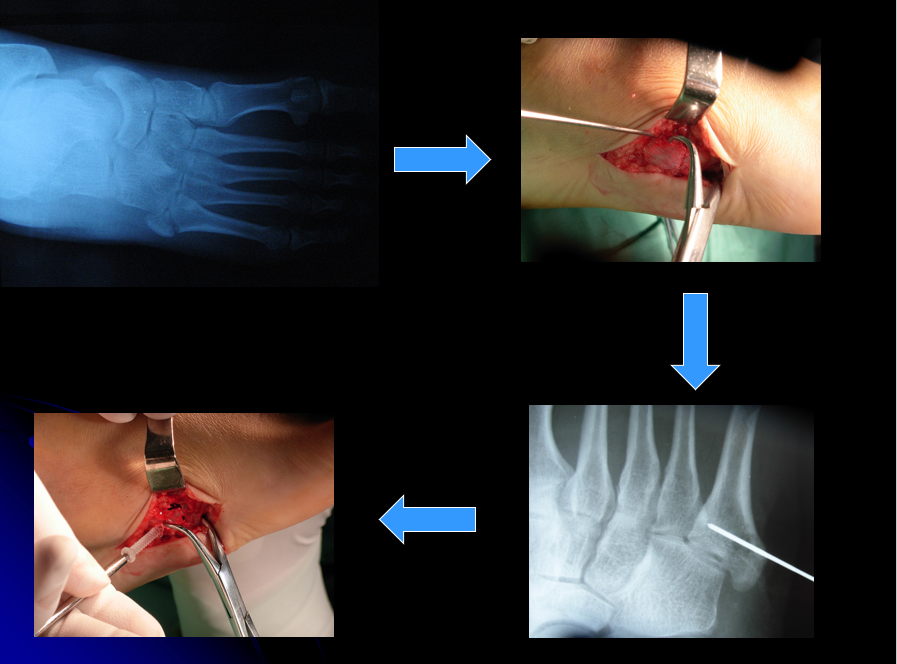

多发足部跖骨骨折手术治疗 梁志军

其它 弹性髓内针技术在儿童跖骨骨折中运用 写美篇完善相关手术前检查

病例讨论左足第1234跖骨骨折